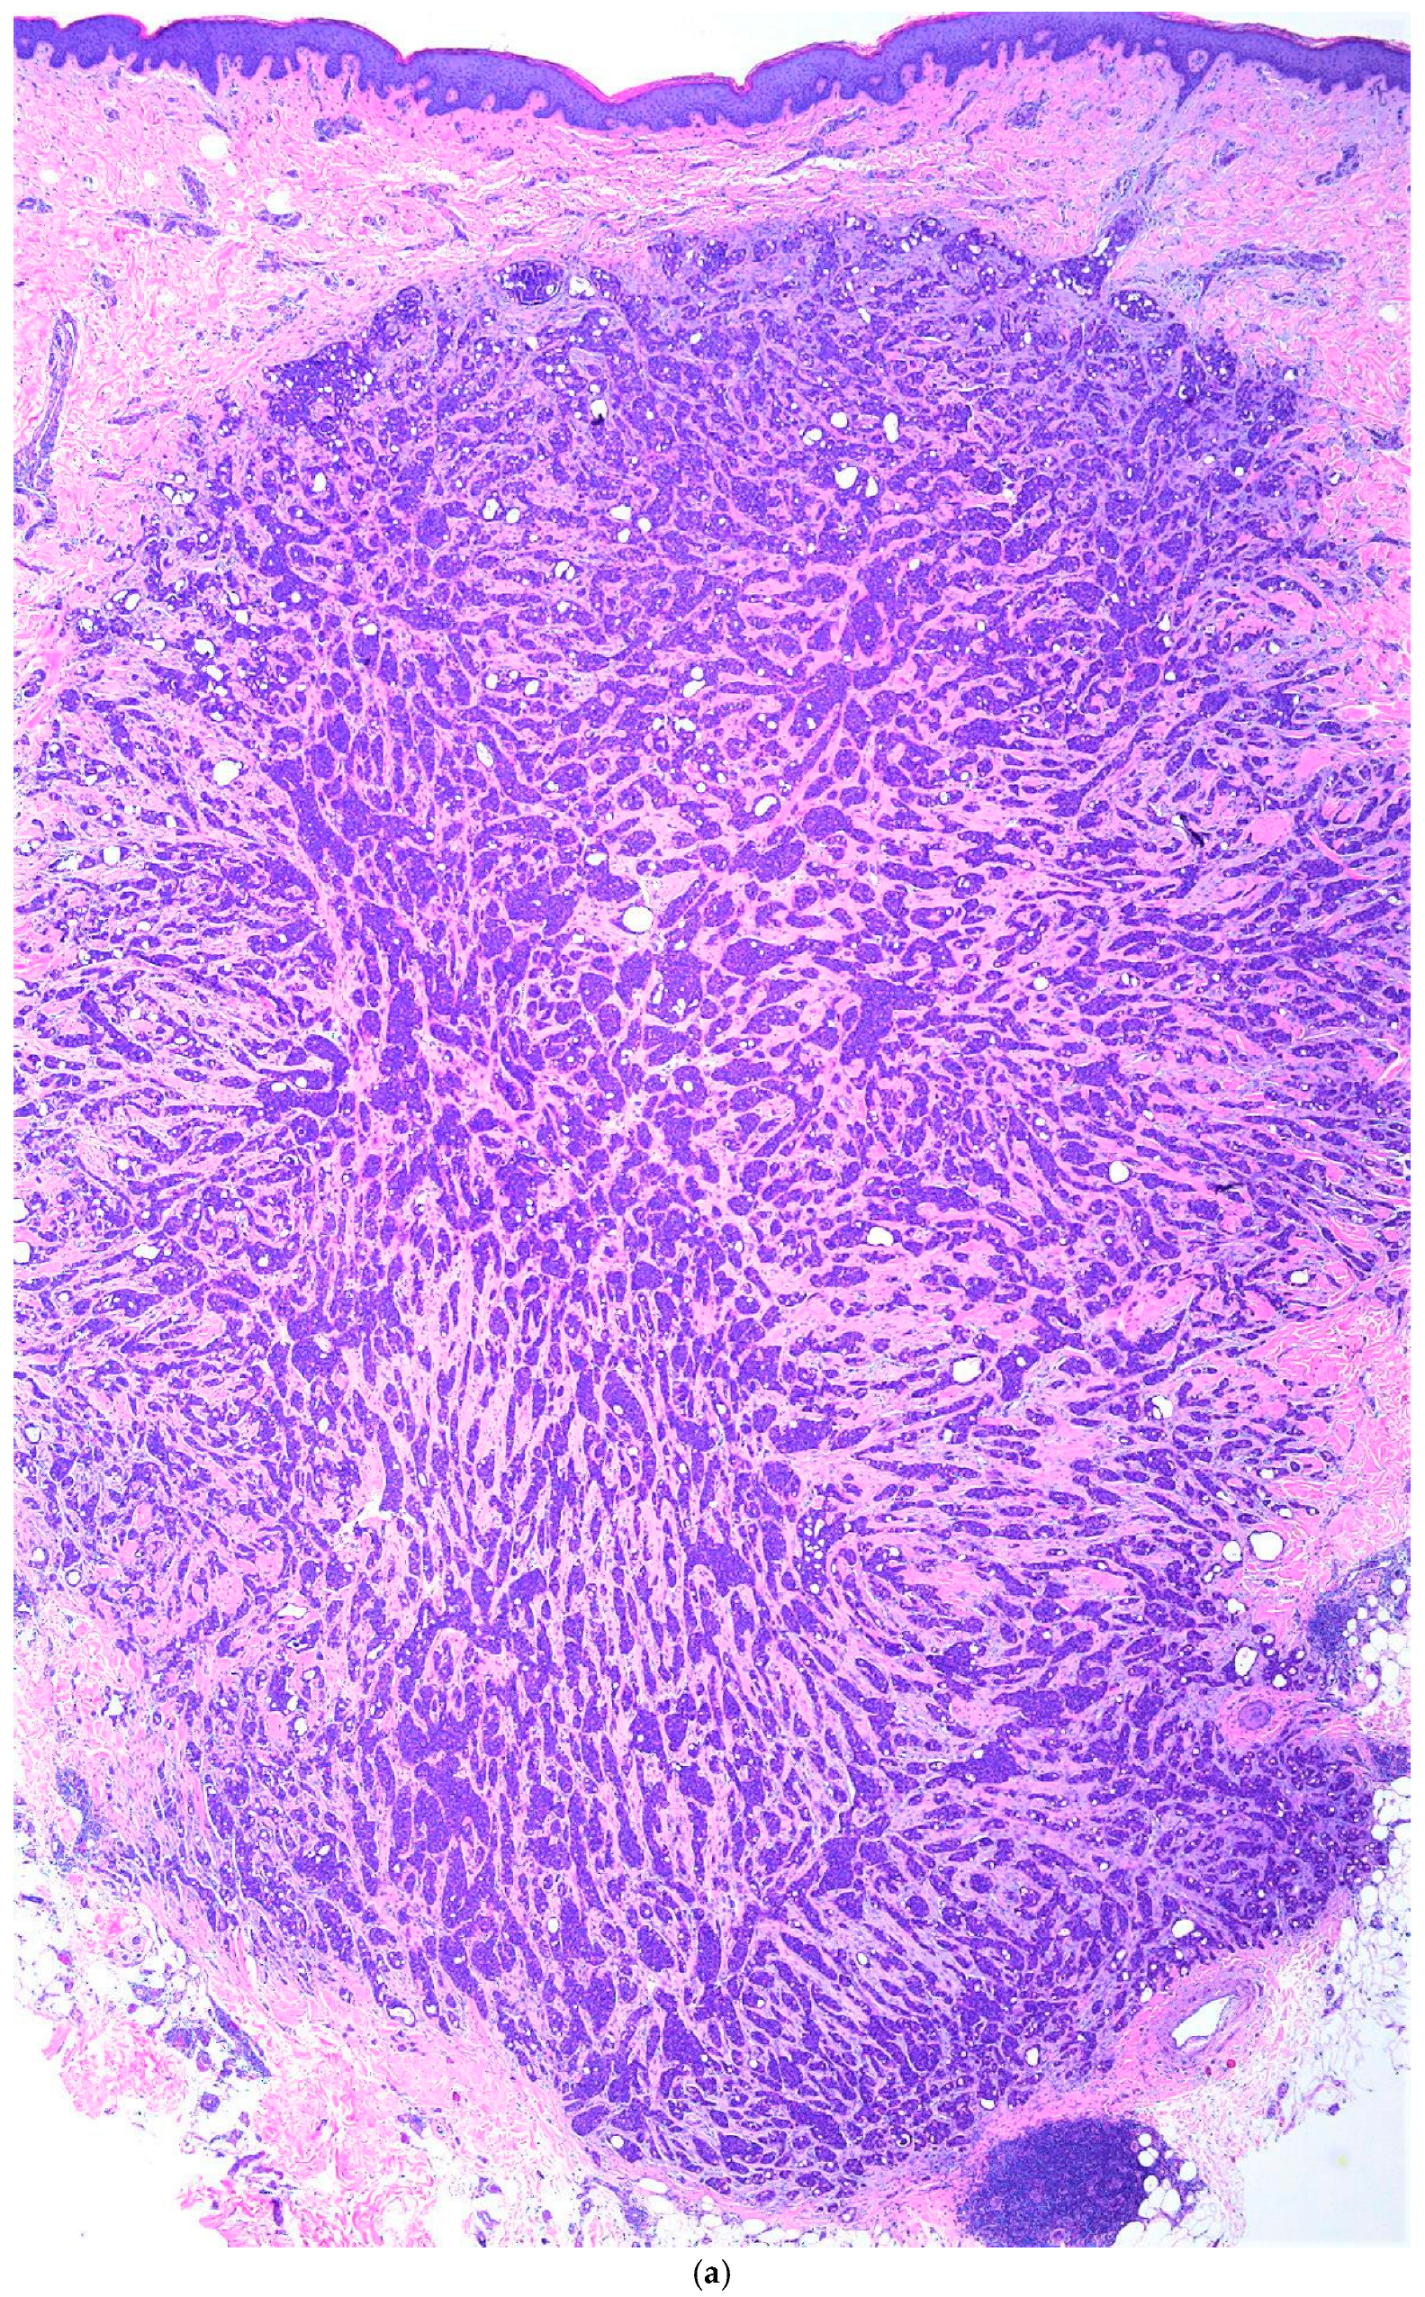

Primary Cutaneous Cribriform Apocrine Carcinoma: A Case Report and Narrative Review

3. Case